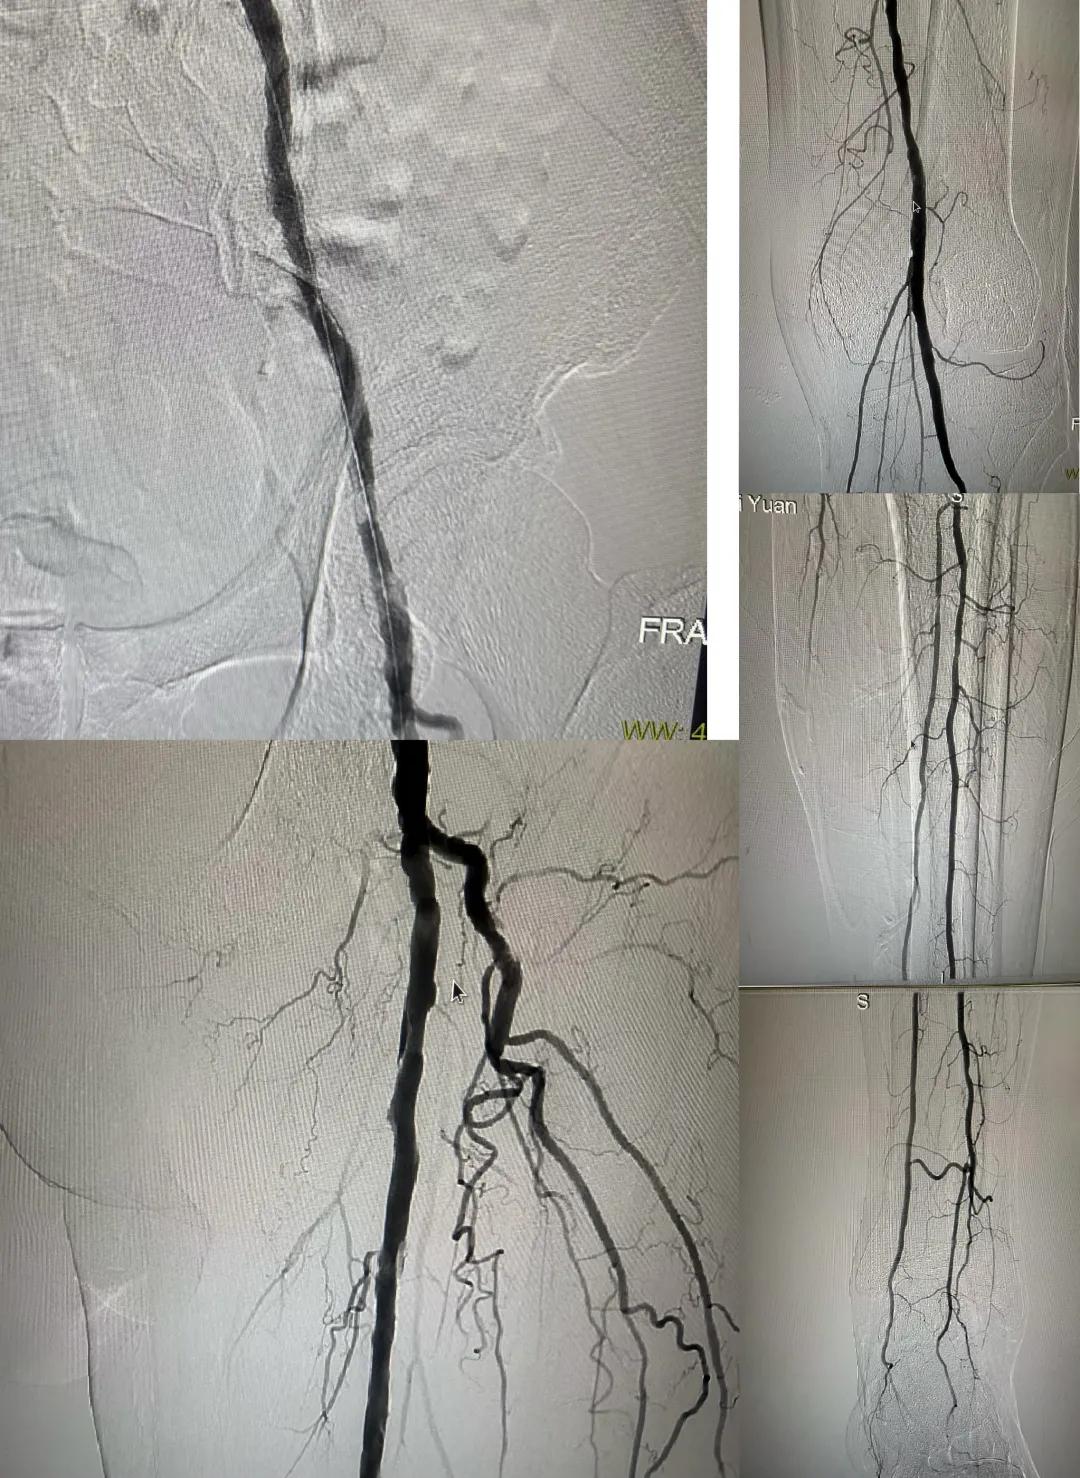

患者,男,73歲,約15天前出現(xiàn)左側(cè)腳面腫痛,間歇性跛行,左足第三足趾壞疽,遂來市中醫(yī)院就診,以“下肢動(dòng)脈硬化閉塞、糖尿病足壞疽、”收住外二科,評估患者病情后需實(shí)施左下肢球囊擴(kuò)張成形術(shù)。術(shù)中造影見患者左側(cè)髂動(dòng)脈、股淺動(dòng)脈階段性重度狹窄。經(jīng)外周球囊擴(kuò)張術(shù)后,再次造影見股淺動(dòng)脈、髂動(dòng)脈血流通暢,膝下及足部血流速度較前改善。

術(shù)后已疏通血管成像

從術(shù)后緩解癥狀到長期的健康益處,手術(shù)不僅是血管解剖結(jié)構(gòu)的修復(fù),更是患者整體健康的轉(zhuǎn)折點(diǎn)。